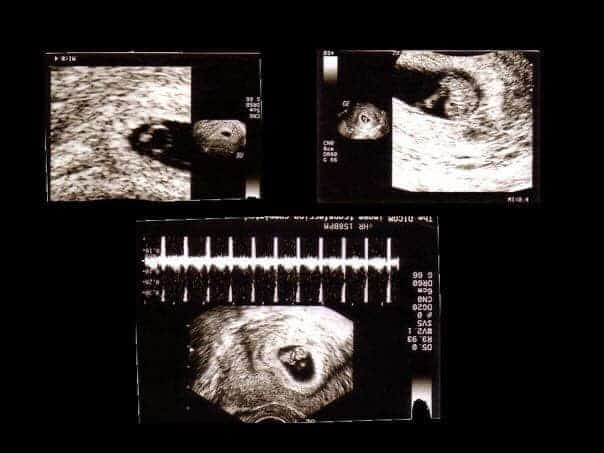

Quando era incinta di cinque settimane, Purington l’ha portata in una clinica  con la speranza che avrebbe scoperto  altre opzioni oltre all’aborto. Era troppo presto per vedere il bambino sullo schermo a ultrasuoni ma sono stati in grado di sentire il battito cardiaco del bambino. Tre settimane dopo, sono tornati per una seconda ecografia e hanno visto il bambino sullo schermo.

“Il nostro bambino aveva dita, manine e piedini”

“Il nostro bambino era a 8 settimane di gestazione e aveva le dita delle mani, dei piedi, gli occhi, tutto”, ha spiegato. “Ho visto e sentito il cuore di mio figlio battere e ho pianto. È stata un’esperienza molto travolgente e bellissima per me, finché lei non mi ha guardato e ha detto: “Per cosa stai piangendo? Anche i vermi hanno il battito del cuore. “

Prima di tutto, i vermi tecnicamente non hanno un cuore nel modo in cui lo hanno gli esseri umani. In secondo luogo, anche a partire dalle otto settimane di gestazione, un essere umano anche prematuro ha gambe, braccia e mani che può muovere. Ha anche un battito cardiaco che è iniziato tra 16 e 21 giorni e ha attività delle onde cerebrali. Secondo alcune ricerche, potrebbe persino essere in grado di rispondere al dolore. È un piccolo essere umano in via di sviluppo.